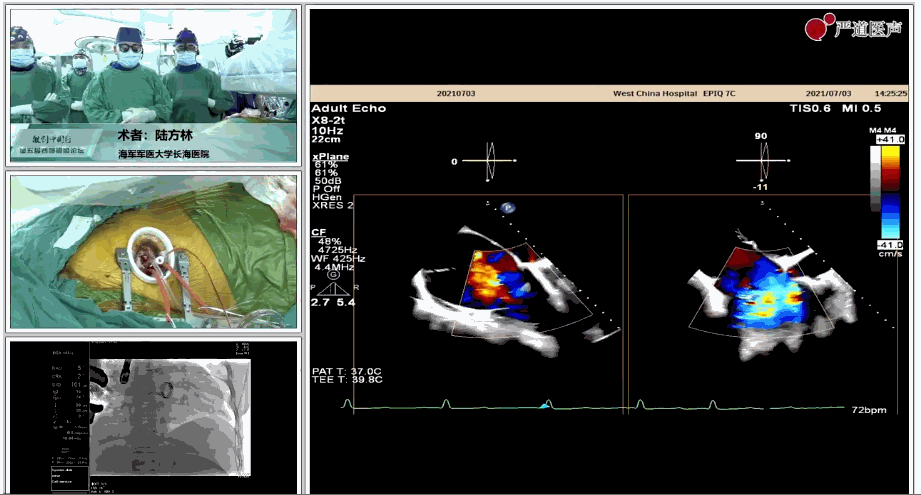

陸方林教授分享的是一例極重度三尖瓣返流的患者采用健世科技(LuX-Valve®)經(jīng)導(dǎo)管三尖瓣置換系統(tǒng)進(jìn)行的手術(shù)直播演示。此例患者為69歲女性,入院前17年行二尖瓣機(jī)械瓣置換術(shù),術(shù)后長期服用華法林抗凝,既往“2型糖尿病”病史5年,“雙下肢水腫”3年。3個(gè)月前患者出現(xiàn)腹脹、雙下肢水腫,伴活動(dòng)后暈厥,伴黃疽、皮膚濕癢、牙齦出血,癥狀持續(xù)加重,遂入院治療。入院后行心臟CT、心臟超聲檢查,提示:“三尖瓣關(guān)閉不全(極重度),二尖瓣置換術(shù)后,心功能III級”。徐志云、陸方林微創(chuàng)三尖瓣置換團(tuán)隊(duì)對該患者的病情進(jìn)行了充分的評估和討論。由于患者有開胸二尖瓣置換手術(shù)史,且病史時(shí)間長,同時(shí)存在相關(guān)合并癥,傳統(tǒng)外科手術(shù)風(fēng)險(xiǎn)極高(STS評分:8.315%),最終決定采用三尖瓣LuX-Valve®瓣膜系統(tǒng)對患者進(jìn)行治療。

圖片

▲術(shù)中食道超聲顯示三尖瓣極重度返流